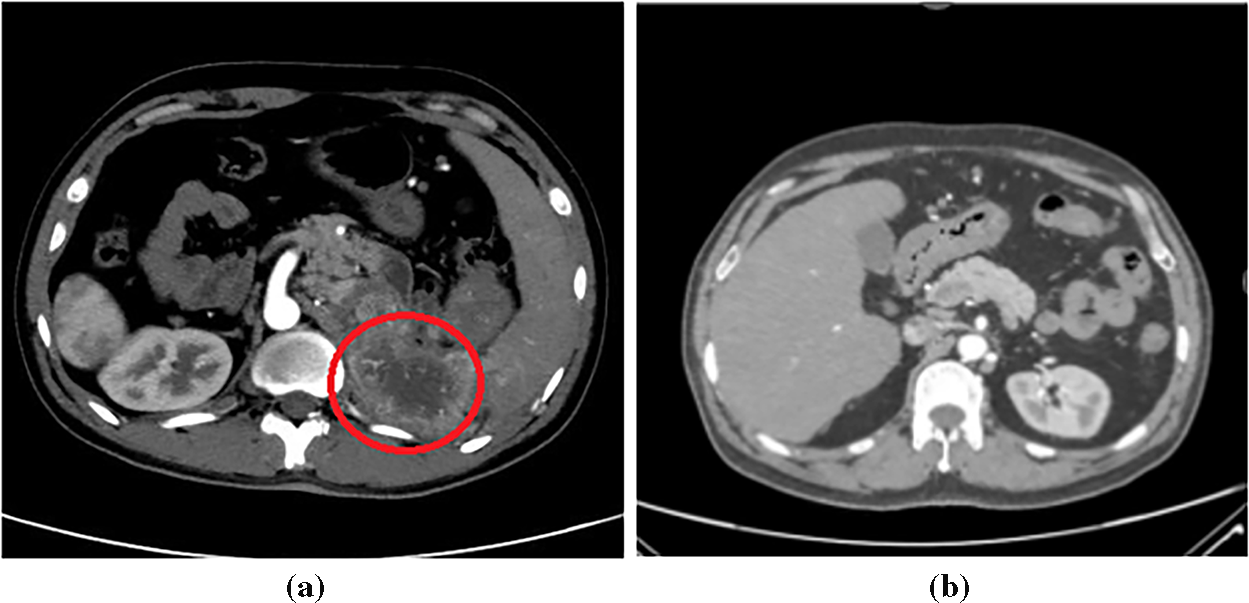

This study employed a publicly available Kaggle dataset [51] of 10,000 labeled kidney CT images, evenly divided between cancerous and normal cases. The images encompass a diverse range of lesion presentations, ensuring comprehensive representation for model development. Fig. 2 illustrates representative CT images from both classes. To ensure ethical compliance and data protection, all dataset files were anonymized prior to use, removing any personally identifiable metadata or patient information. While the Kaggle dataset is publicly available, it was handled under privacy-preserving principles consistent with medical data governance standards such as HIPAA (Health Insurance Portability and Accountability Act) and GDPR (General Data Protection Regulation). In potential clinical deployment, data encryption and controlled access mechanisms would be essential to maintain patient confidentiality and prevent unauthorized access.

Figure 2: Sample kidney CT images: (a) Cancerous; (b) Normal